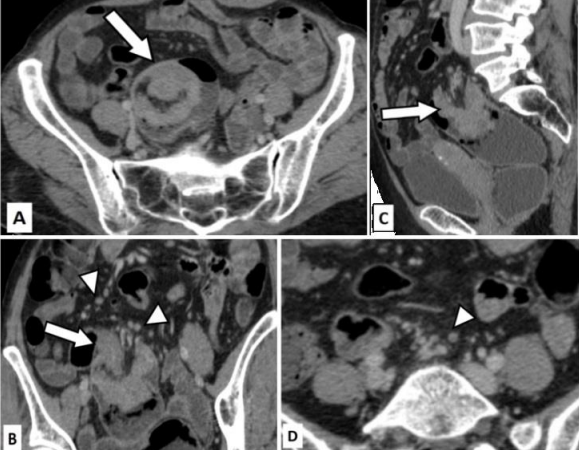

Figure 3: True positive for T4 disease and false positive for nodal involvement.

Case of 45 years old male who presented to the emergency room with pain in abdomen and distension.

Figure 3A (axial) and 3B (sagittal) CT images in venous phase show a relatively well-defined cavitating mass (white arrow) arising from the sigmoid colon. Fistulous communication with anterior ileal loops can be seen (black arrow).

Figure 3C (axial CT image in venous phase) shows multiple dilated small bowel loops with air fluid levels suggestive of obstruction. Arrowhead points to an enlarged para-aortic lymph node with calcification. Figure 3D (axial CT image in venous phase) shows diffuse fatty liver with multiple small sub centimetric hypo enhancing nodules suggestive of micrometastasis. A larger hypo enhancing lesion was seen in the left lobe(arrow).  Palliative surgery was performed and the post-operative histopathology revealed T4 disease of the primary tumor. The para-aortic node was negative for malignancy.